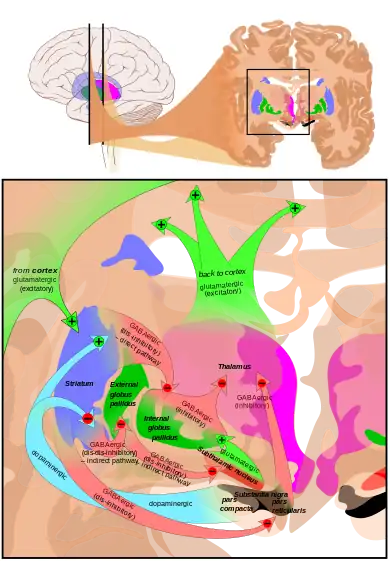

[31] The largest connection is from the cortex, in terms of cell axons. Many parts of the neocortex innervate the dorsal striatum. The cortical pyramidal neurons projecting to the striatum are located in layers II-VI, with the most dense projections come from layer V.[32] They end mainly on the dendritic spines of the spiny neurons. They are glutamatergic, exciting striatal neurons.

Another well-known afferent is the nigrostriatal connection arising from the neurons of the substantia nigra pars compacta. While cortical axons synapse mainly on spine heads of spiny neurons, nigral axons synapse mainly on spine shafts. In primates, the thalamostriatal afferent comes from the central median-parafascicular complex of the thalamus (see primate basal ganglia system). This afferent is glutamatergic. The participation of truly intralaminar neurons is much more limited. The striatum also receives afferents from other elements of the basal ganglia such as the subthalamic nucleus (glutamatergic) or the external globus pallidus (GABAergic).

The primary outputs of the ventral striatum project to the ventral pallidum, then the medial dorsal nucleus of the thalamus, which is part of the frontostriatal circuit. Additionally, the ventral striatum projects to the globus pallidus, and substantia nigra pars reticulata. Some of its other outputs include projections to the extended amygdala, lateral hypothalamus, and pedunculopontine nucleus.[36]

The main nucleus of the basal ganglia is the striatum which projects directly to the globus pallidus via a pathway of striatopallidal fibers.[37] The striato-pallidal pathway has a whitish appearance due to the myelinated fibers. This projection comprises successively the external globus pallidus (GPe), the internal globus pallidus (GPi), the pars compacta of the substantia nigra (SNc), and the pars reticulata of substantia nigra (SNr). The neurons of this projection are inhibited by GABAergic synapses from the dorsal striatum. Among these targets, the GPe does not send axons outside the system. Others send axons to the superior colliculus. Two others comprise the output to the thalamus, forming two separate channels: one through the internal segment of the globus pallidus to the ventral oralis nuclei of the thalamus and from there to the cortical supplementary motor area and another through the substantia nigra to the ventral anterior nuclei of the thalamus and from there to the frontal cortex and the occulomotor cortex.